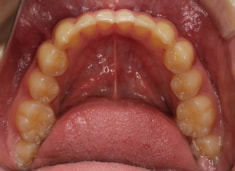

小児期ケース:反対咬合+上顎両側3番埋伏歯

(受け口+3番目の永久歯が左右両方とも埋まってしまい、はえてこない)

治療法:上顎急速拡大装置+クリアスナップ+フェイスマスク+上顎3番は開窓牽引CT写真にて位置確認

治療開始時